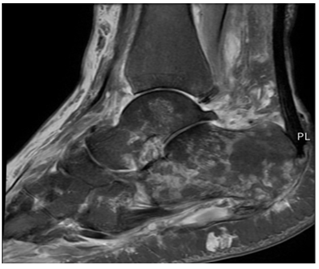

Plain radiographs were inconclusive. Magnetic resonance imaging (MRI) with contrast revealed heterogeneous bone marrow signals consistent with osteomyelitis. Computed tomography (CT) imaging showed scattered hyperdense areas and a moth-eaten appearance in both the talus and calcaneus (Figure 2). Blood cultures at the time of admission were negative. Pathological analysis confirmed septic arthritis of the ankle joint and persistent acute osteomyelitis of the talus and calcaneus. The radiologic and clinical findings suggested contiguous spread from the calcaneus to the talus and ankle joint, likely through the subtalar joint, a recognized anatomic pathway for infection progression in the hindfoot.

Figure 2 CT scan of right foot showing scattered areas of hyperdensity in the talus and calcaneus with a moth-eaten appearance.